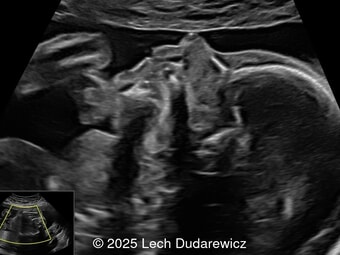

A 36-year-old pregnant woman with non-contributory anamnesis was referred to our center at 12 weeks and 6 days of gestation following suspicion of fetal abnormalities on a routine first-trimester (11โ14 weeks) scan performed elsewhere.

Ultrasound findings are presented below.ย What is the most likely diagnosis?